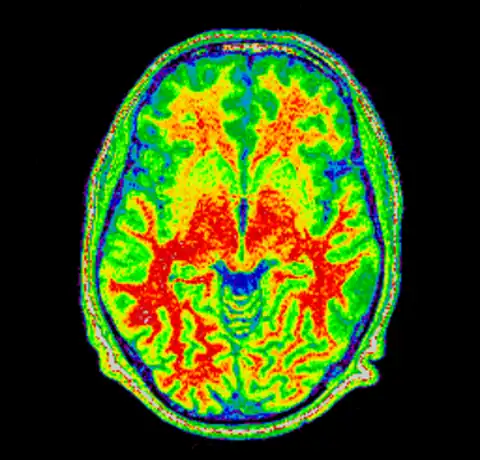

We can now take a look at the corrected file (out.mnc)

As it is very hard to pick the differences between the original and corrected version we can create a field image to visualise the differences.

And then for completeness sake, here are the original and corrected image using a spectral colormap to better visualise the change. Note that in the second (corrected) image the intensity of the white matter is more uniform (the red part).